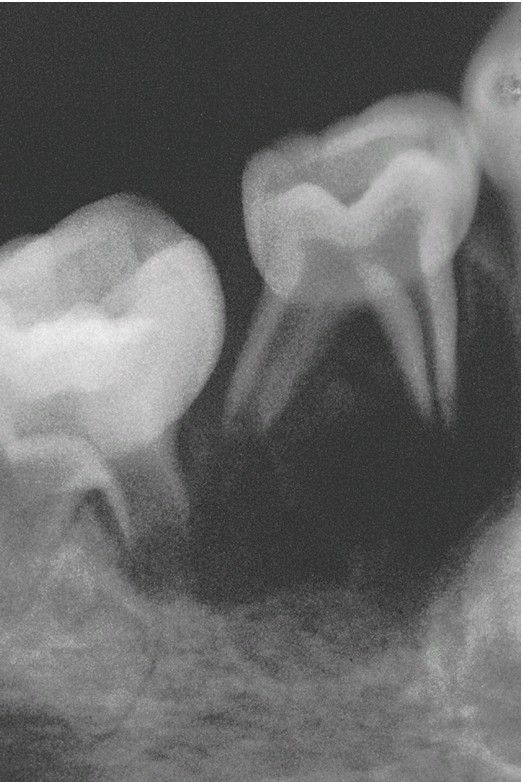

Langerhans Cell Histiocytosis.

Periapical radiograph showing marked bone loss involving the mandibular teeth in a young girl, resulting in a “floating-in-air” appearance of the teeth.